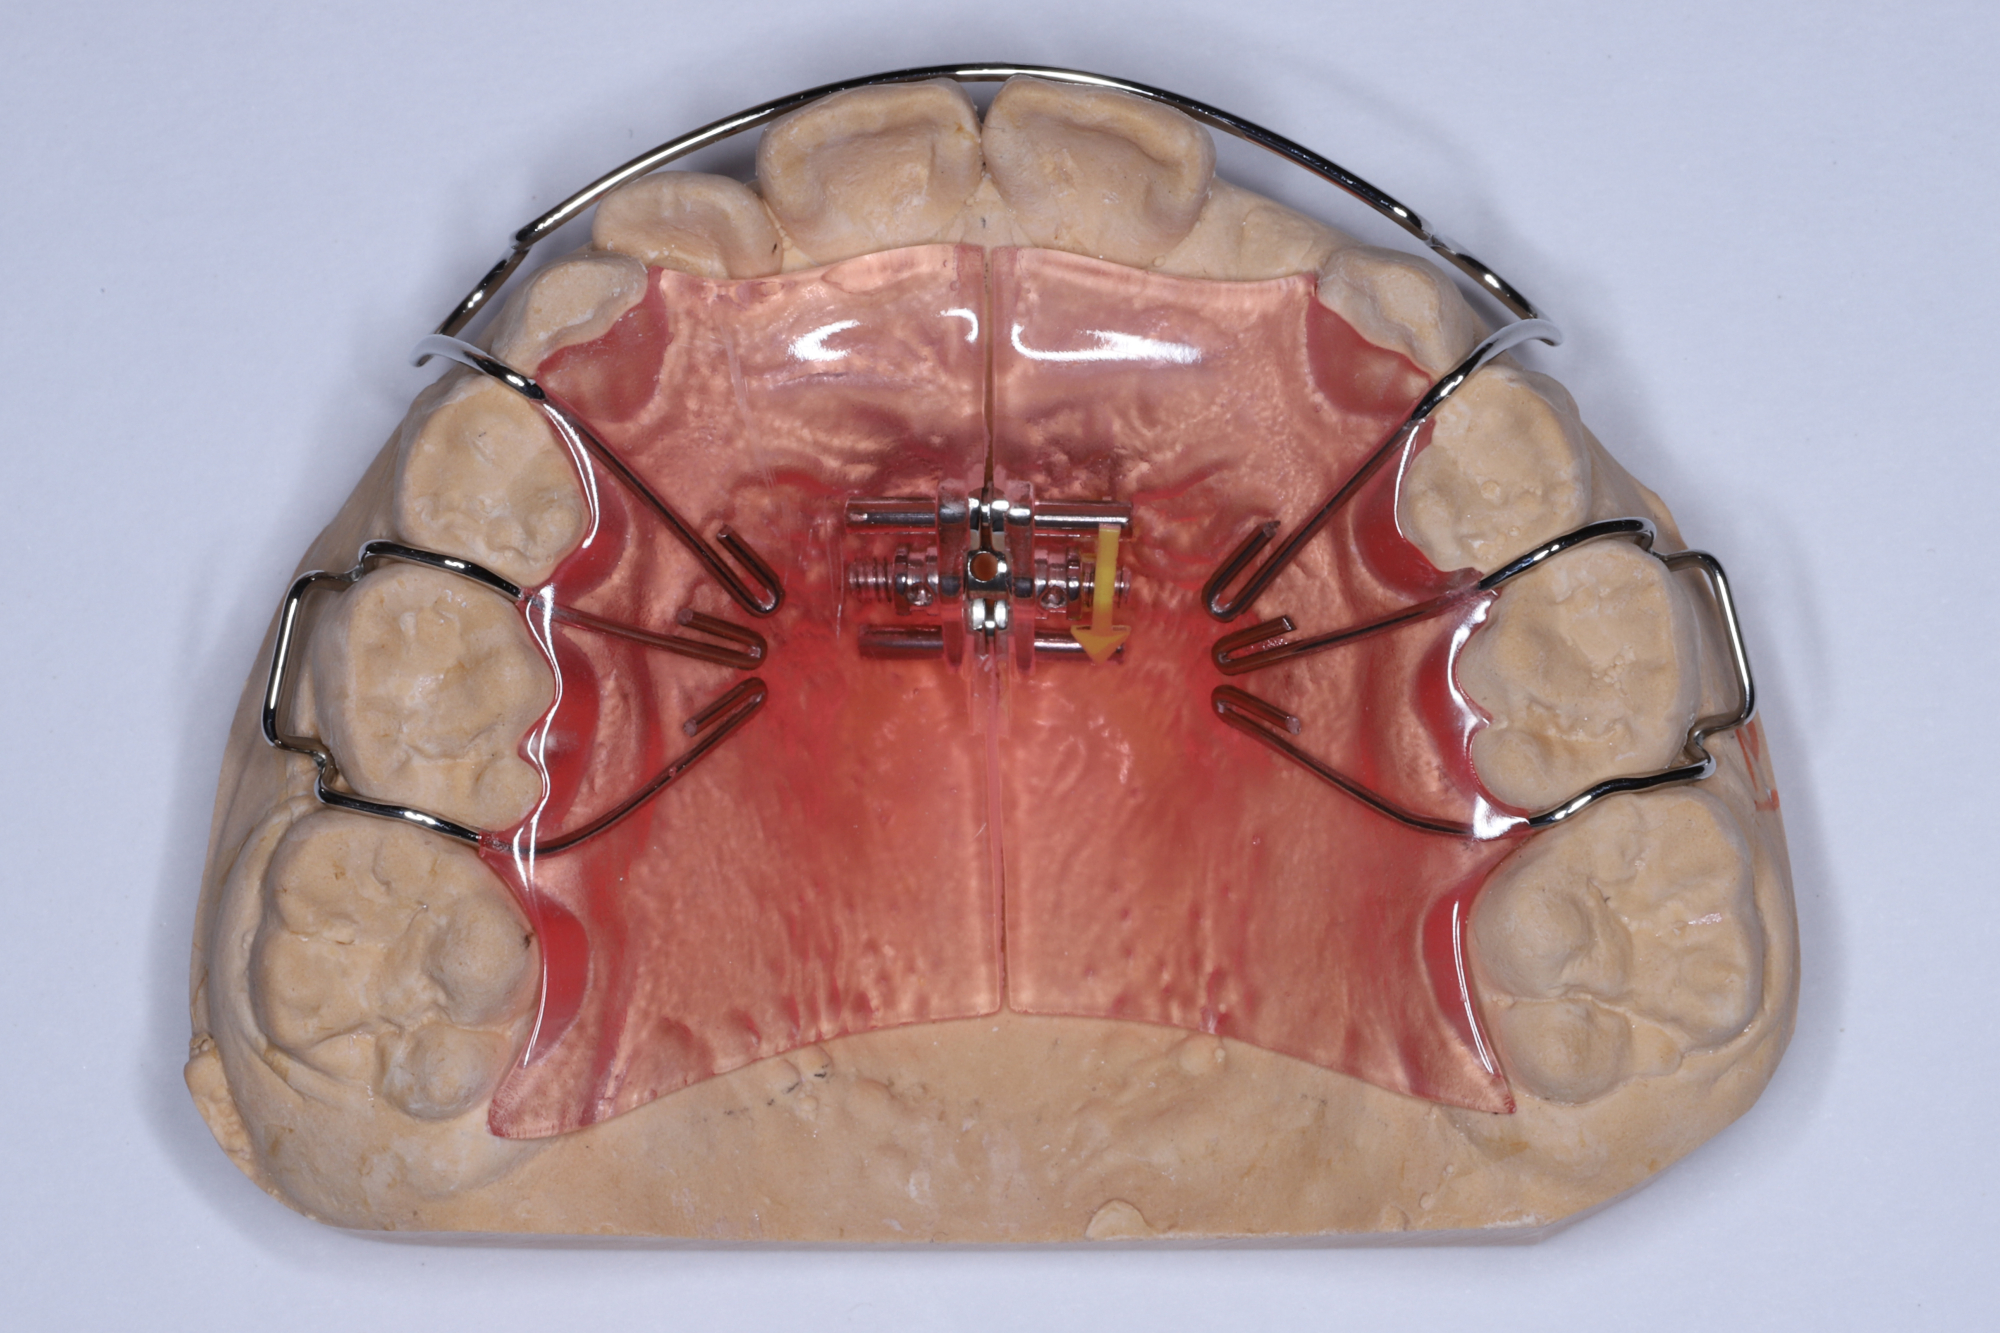

拡大床治療は以前よりヨーロッパを中心に行われていた治療法であり、いろいろな形の装置が用いられていました。 それらを整理し治療目標に応じてまとめたのがウィーンの歯科医シュワルツであり1938年に一冊の教科書にまとめたことでシュワルツの拡大装置と呼ばれるようになりました。 社会保障の充実したヨーロッパの各国では家庭で簡単にできる矯正治療法として広まり、北欧など自然環境が厳しい地域では通院回数が少なくて済む拡大床治療が一般開業医で保険診療として多く行われるようになりました。一方アメリカでは永久歯を抜歯してスペースを作り歯を画一的にキレイに並べる方法が確立され主流になっているため拡大床治療のように時間がかかり患者の装着状況によって治療結果が左右するような治療が行われることがありません。日本の歯科矯正治療学は歴史的にアメリカからの流れで発展してきたため矯正歯科専門で治療を行っている先生方の間では拡大床治療はあまり勧められていないのが現状です。簡単に云うと歯を抜かずに時間をかけて治療をするのがヨーロッパ的で、歯を抜いて短期間で完璧にキレイに歯を並べるのがアメリカ的と言えます。どちらの治療法も正しいと思いますのでご家庭、お子さんに合わせて治療法を選択する必要があります。

日本で行われている拡大床治療にも色々な方法がありますが当院での特長は最初に永久歯に生え替わる上下4本の前歯を奥歯の生え替わりが始まる前までに顎を拡大してきれいに並べることです。そのため拡大床治療の期間は小学校1年生頃から4、5年生頃までの間に限定しており、それまでに目的が達成できない場合には別の治療法に移行します。またゆっくりスペースを獲得するようにしているのも特長で2週間に1回ネジを回すようにしています。一般的には1週間にⅠ回ないし2回ネジを回すことが多いようです。ゆっくり進めるので一日の装着時間はお家にいるときと寝ている間だけにしています。学校や自宅以外での装着はせずゆっくり拡大していくので治療期間が長くなりますが後戻りは少なく確実になります。治療開始時期が大切ですので時期を逸した場合には拡大床治療は行いません。一般的に拡大床治療の評判が悪いのは開始時期が遅く、いつまでも治療を長引かせ治らないことによるものが多いようです。 拡大床治療はスペースを作って永久歯がならぶスペースを作ることが目標ですので細かい歯の向きや角度まで整えられないこともあります。そんな場合には別の矯正治療が必要になります。